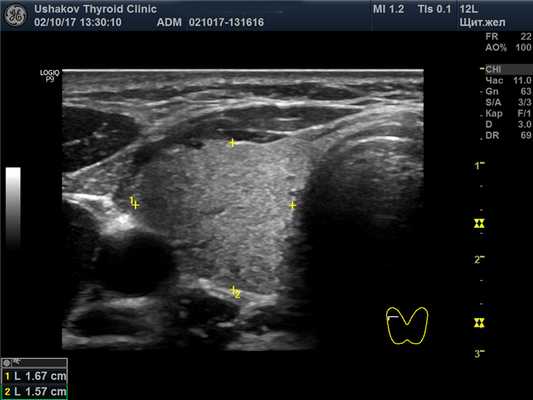

Присутствуют обе доли и перешеек щитовидной железы; расположение типично. Граница и контур чёткие.

Структура паренхимы долей щитовидной железы неоднородная – узловая, вне узлов преобладает изоэхогенность.

В правой доле щитовидной железы в центрально-каудальной части почти до её краев (в поперечной проекции) расположен овоидоподобной формы узел 22,9х20,7х33,1 мм (7,4 мл), окруженный по всему периметру чёткой гипоэхогенной границей-контуром, значительно неоднородный за счет множественных анэхогенных (жидкостных) участков (около 70% от объёма узла), преимущественно с чёткими границами в виде узких перегородок с изо- и гиперэхогенной (фиброзной) тканью и изоэхогенной тканью по периметру узла; при ЭДК заметно примыкание к узлу с кранио- и каудальной сторон магистральных сосудов, и умеренный кровоток по части периметра и мало интенсивный внутри узла (в перегородках); при эластографии SR 2,8 (3,3 - в обл. некоторых перегородок). Вне узла ткань изоэхогенная, почти однородная; в краниальном полюсе 21,2х15х15,1 мм (2,3 мл), а также медиально. В режиме ЦДК и ЭДК кровообращение в этой ткани в малой степени усилено.

Внеузловая ткань. У пациентки внеузловая ткань железы выглядит почти абсолютно нормальной, гормонообразующей. Эта ткань занимает всю левую долю, за исключением двух малых узлов, объём которых так мал, что им можно пренебречь (рис. 27.1-27.4).

Рис. 27.1. Пример 1. (левая доля, поперечная проекция).

Ткань доли и перешейка изоэхогенная, почти однородная. Граница железы чёткая.

Рис. 27.5. Пример 1. (правая доля, поперечная проекция).

Латерально и вентрально за узлом – лишь тонкий слой ткани. Медиально заметна значимая часть внеузловой ткани. Узел в поперечной проекции подобен кругу. Чёткий гипоэхогенный контур по всему периметру узла.